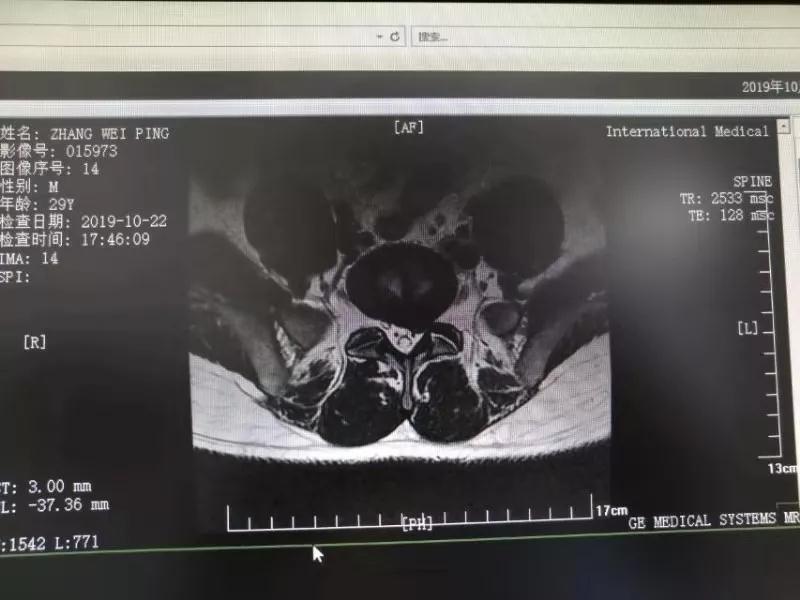

10月25日,29歲的患者小張了解到西安國(guó)際醫(yī)學(xué)中心骨科醫(yī)院專(zhuān)家云集,一大早便在家人的陪同下,來(lái)到西安國(guó)際醫(yī)學(xué)中心骨科醫(yī)院就診?!拔已闯掷m(xù)2年多,最近感冒后腰痛癥狀明顯加重了?!毙埫媛犊喑?,因?yàn)殚L(zhǎng)期腰痛、左下肢放射性疼痛,她晚上睡覺(jué)不能平躺,經(jīng)常疼得睡不著,需要口服止痛藥物才能有所緩解。走路走不了多遠(yuǎn)就開(kāi)始腿抽的疼,嚴(yán)重影響到工作和生活。

結(jié)合患者的檢查以及年齡情況,王自立副院長(zhǎng)推薦讓專(zhuān)門(mén)研究椎間孔鏡技術(shù)王雄勛主任給小張做微創(chuàng)的椎間孔鏡手術(shù)。該手術(shù)創(chuàng)傷很小,不影響脊柱的穩(wěn)定性,尤其適合于椎間盤(pán)突出的年輕患者,懷著對(duì)骨科醫(yī)院專(zhuān)家的信任,小張與家人商議后,接受手術(shù)治療。